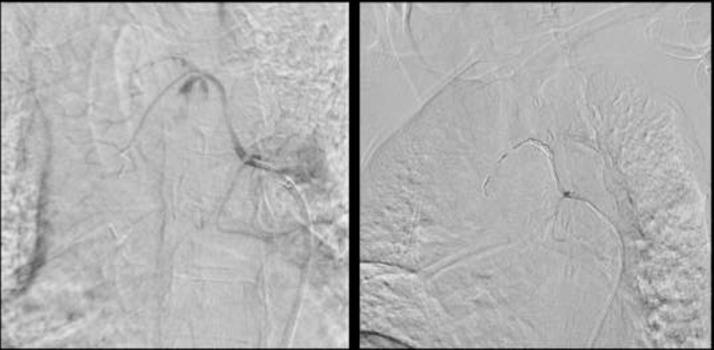

Bronchial artery aneurysm and pseudoaneurysm is a rare but life-threatening diagnosis due to catastrophic complications from rupture. Prompt detection and management is key to prevent complications. CT angiogram and digital subtraction angiography are preferred diagnostic imaging modalities. Being very uncommon, these entities can be misdiagnosed as a nonspecific mediastinal soft tissue mass, which can lead to delay in diagnosis and inappropriate or delayed management. We present a case of 72-year-old woman with incidentally detected large bronchial artery pseudoaneurysm, incorrectly classified as mediastinal malignancy at outside facility, receiving follow-up exams for 2 years, before correct diagnosis and management.

支气管动脉动脉瘤和假性动脉瘤是一种罕见但危及生命的诊断,因为破裂会引发灾难性并发症。及时检测和处理是预防并发症的关键。CT血管造影和数字减影血管造影是首选的诊断成像方式。由于非常罕见,这些病变可能被误诊为非特异性纵隔软组织肿块,从而导致诊断延迟以及治疗不当或延误。我们报告一例72岁女性病例,其偶然发现巨大支气管动脉假性动脉瘤,在外院被错误分类为纵隔恶性肿瘤,接受了2年的随访检查,最终才得以正确诊断和处理。